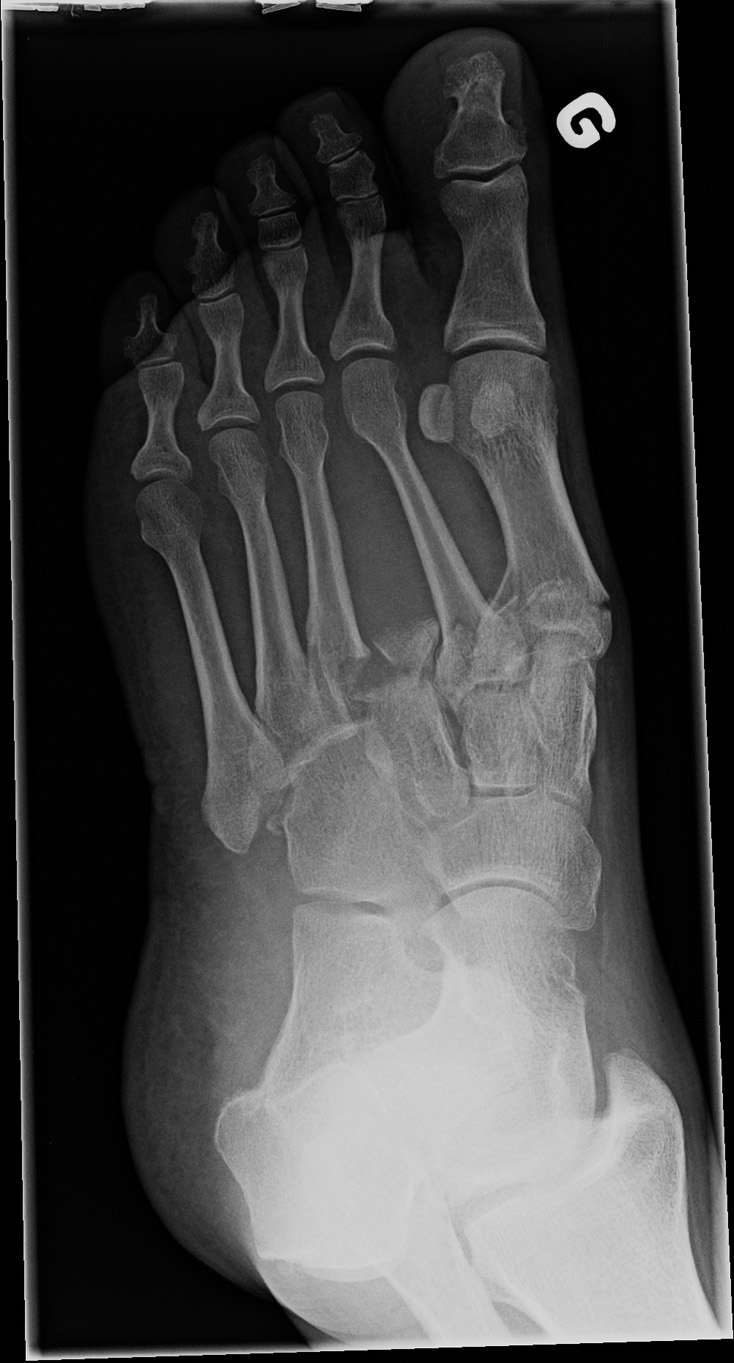

54-year-old male:

High velocity car crash.

Lisfranc fracture

First, note the base fractures of the 1st and 2nd metatarsal bones, minimally displaced, yet angulated in valgus. Second, note the three lateral metatarsal bones laterally displaced and with a varus angulation; the 3rd one is fractured and the 4th and 5th ones are dislocated. Thus, this is a Lisfranc fracture-dislocation of the divergent type. However, this is actually an atypical Lisfranc injury, for the 1st and 2nd metatarsals are both displaced medially and the 3rd, 4th and 5th are displaced laterally. In a classic Lisfranc injury, only the 1st metatarsal deviates medially, while the 2nd, 3rd, 4th and 5th are all displaced laterally.

4th metatarsal alignment

On the oblique view, the cuboid's medial body is no longer aligned with the 4th metatarsal's medial border. The 3rd metatarsal can now be seen in its stead.

Bony fragment

Multiple bony fragments of the 3rd metatarsal base can be seen between the 2nd and 3rd metatarsal bones.

Oblique